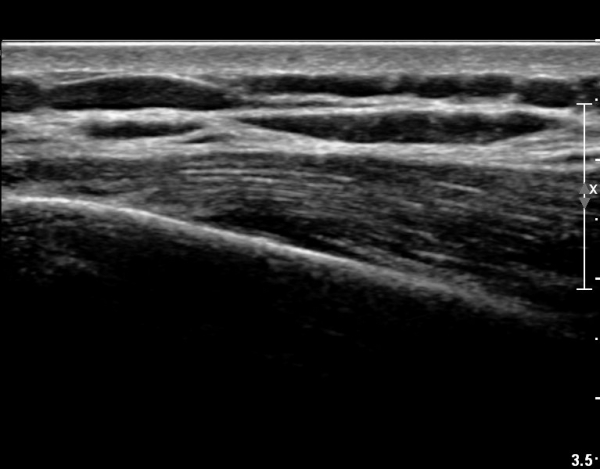

8¹øÂ° °¥ºñ»À ¾ÕÂÊ Á¾´Ü¸é°Ë»ç»ó ƯÀÌ ¼Ò°ßÀ» º¸ÀÌÁö ¾ÊÀ¸¸¶(»çÁø 4)

ŽÃËÀÚ¸¦ µÚÂÊÀ¸·Î À̵¿ ÇÏ´Ï °¥ºñ»À Ç¥ÃþÀ¸·Î Àú¿¡ÄÚ ºÎÁ¾ÀÌ °üÂûµÈ´Ù(»çÁø 3).